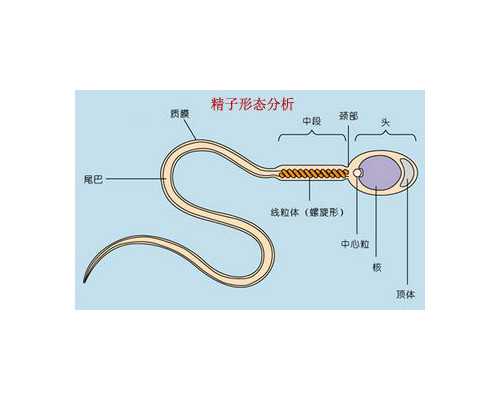

溫馨提示

取卵前打hcg的作用是為了促進(jìn)卵泡進(jìn)行排卵,HCG的主要作用就是誘發(fā)成熟卵泡中的卵母細(xì)胞最后成熟,而HCG在正確的時(shí)機(jī)使用才能獲得理想的治療效果,一般是在卵泡達(dá)到18mm左右停用促排藥物,在最后一次藥物使用后的36小時(shí)左右注射HCG,HCG注射后36-37小時(shí)內(nèi)完成取卵手術(shù)。